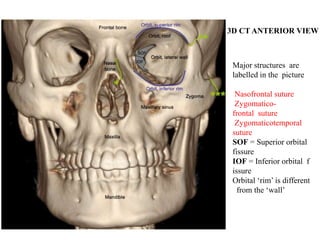

3D CT ANTERIOR VIEW

Major structures are

labelled in the picture

Nasofrontal suture

Zygomatico-

frontal suture

Zygomaticotemporal

suture

SOF = Superior orbital

fissure

IOF = Inferior orbital f

issure

Orbital ‘rim’ is different

from the ‘wall’